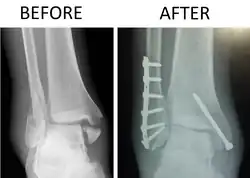

Quando um trauma físico causa três ou mais sintomas de fraturas um raio X de frente e perfil deve ser feito. Uma tomografia pode ser solicitada para ver os detalhes antes e depois de uma cirurgia.

O reparo cirúrgico é uma redução ortopédica (reposicionamento dos ossos), osteossíntese com placa e parafusos e imobilização com gesso. Nos primeiros duas semanas sem andar e nas quatro semanas seguintes com bota de gesso, que permite pisar. Em idosos o prazo é o dobro (quatro semanas sem pisar, mais oito semanas com bota de gesso). O tratamento não cirúrgico pode ser considerado nos casos em que o paciente tem problemas de saúde significativos que desaconselham uma grande cirurgia.[3]